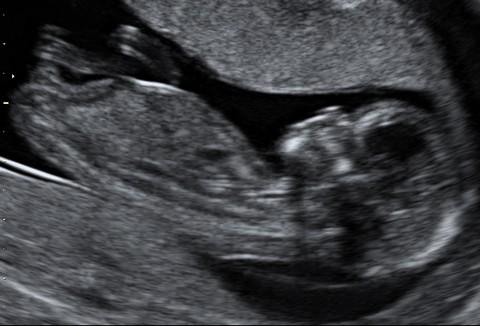

14. týdnem začíná 2. trimestr těhotenství. V tomto týdnu měří plod zhruba 8,5 cm. Při zjišťování délky plodu se měří vzdálenost od temene ke kostrči. Plod nyní váží zhruba 45 gramů.

Plod o velikosti 81 mm ve 14. týdnu těhotenství (13+5)